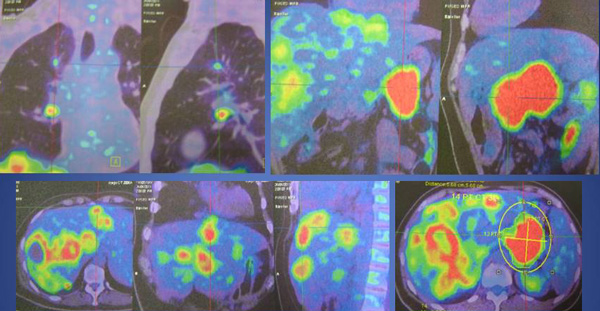

SH said she was well all these years and her progress was monitored by her doctor. About 10 years later, in early 2009, SH developed shortness of breath. She could not lift her left arm. She was tired and lost her appetite. A chest X-ray indicated large left pleural effusion. SH had the fluid in her lung tapped out. A CT scan on 7 January 2009 indicated several subcentimeter nodules in her left lung. The lymph nodes in the left axilla and aortopulmonary window were enlarged. Impression: left pulmonary and pleural metastasis.

A bone scan done on 29 January 2009 indicated multiple skeletal metastases in the sternum and two ribs on the left side.

In August 2011 SH developed shortness of breath again. A CT scan on 4 August 2011 confirmed presence of mild left pleural effusion. Fluid was tapped out of her lung again.

A bone scan done on 18 March 2011 indicated “sclerotic bone metastases in manubrium showing activity.” SH was told that if Aromasin did not work for her, she would have to undergo intravenous chemotherapy.